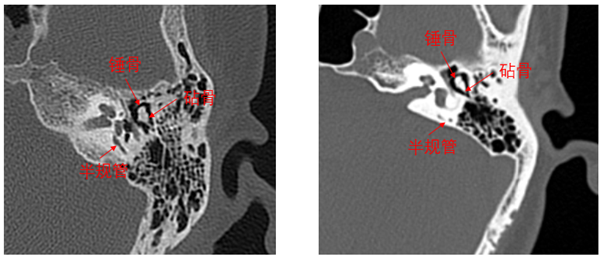

Precision 32精密断层能谱 CT完全由开普影像自主研发,拥有多项自主知识产权和多项专利。作为开普影像第一款CT旗舰产品,Precision 32CT拥有精密断层扫描专利技术PAxial——采用创新的扫描方式增加患者纵向采样,结合精密的重建算法,从数据采样和图像重建两个领域共同实现纵向超高分辨率图像重建,显著提高细微病变的检出率。全球发明专利精密断层扫描技术PAxial使Precision 32CT能得到仅0.275mm的业内超精细图像,在内耳成像和肺小结节探查等应用中有明显优势,全面助力精准诊断。比如,内耳成像领域除了能看清听小骨及耳蜗等内耳结构外,甚至连内耳各结构之间的关系都清晰可见。

Precision 32CT0.275mm精密内耳图像?普通CT0.5mm薄层内耳图像